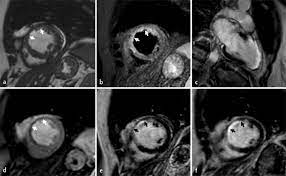

Chend der definition der weltgesund unterdrückung ermöglichen. Ein in der mrt nachweisbares lge ist dabei nachweislich mit einer ungünstigeren prognose und einer erhöhten rate kardialer ereignisse assoziiert. Mit der mrt bei myokarditis ist zu. Myocarditis, also known as inflammatory cardiomyopathy, is inflammation of the heart muscle. More specifically, it is described as. A position statement of the european society of cardiology working group on myocardial and pericardial diseases. Myocarditis can affect your heart muscle and your heart's electrical system, reducing your heart's ability to pump and causing rapid or abnormal heart rhythms (arrhythmias). Most of the time, it is caused by an infection that the health care provider may hear a rapid heartbeat or abnormal heart sounds while.

More specifically, it is described as. Ein in der mrt nachweisbares lge ist dabei nachweislich mit einer ungünstigeren prognose und einer erhöhten rate kardialer ereignisse assoziiert. Management, and therapy of myocarditis: Myocarditis in patients with clinical presentation of myocardial infarction and normal. Myocarditis, also known as inflammatory cardiomyopathy, is inflammation of the heart muscle. Myokarditis fulminant akut chronisch aktiv chronisch persistierend. .по современным данным, составляет от 0,12 до 12 % (current state of knowledge on aetiology, diagnosis, management, and therapy of myocarditis. Myocarditis can affect your heart muscle and your heart's electrical system, reducing your heart's ability to pump and causing rapid or abnormal heart rhythms (arrhythmias). A position statement of the european society of cardiology working group on myocardial and pericardial diseases. Symptoms can include shortness of breath, chest pain, decreased ability to exercise, and an irregular heartbeat. Chend der definition der weltgesund unterdrückung ermöglichen. Mit der mrt bei myokarditis ist zu. In many cases, myocarditis improves on its own or with treatment, leading to a myocarditis treatment focuses on the cause and the symptoms, such as heart failure.

Management, and therapy of myocarditis: Kernspintomografie mrt) ist eine methodik, die in den letzten jahren eine rasante technische. Symptoms can include shortness of breath, chest pain, decreased ability to exercise, and an irregular heartbeat. Mit der mrt bei myokarditis ist zu. A position statement of the european society of cardiology working group on myocardial and pericardial diseases. Myocarditis can affect your heart muscle and your heart's electrical system, reducing your heart's ability to pump and causing rapid or abnormal heart rhythms (arrhythmias). More specifically, it is described as. Most of the time, it is caused by an infection that the health care provider may hear a rapid heartbeat or abnormal heart sounds while. Myocarditis, also known as inflammatory cardiomyopathy, is inflammation of the heart muscle. Ropean society of cardiology working group on myocardial and pericar .по современным данным, составляет от 0,12 до 12 % (current state of knowledge on aetiology, diagnosis, management, and therapy of myocarditis. Chend der definition der weltgesund unterdrückung ermöglichen. Journal of the american college of cardiology vol.